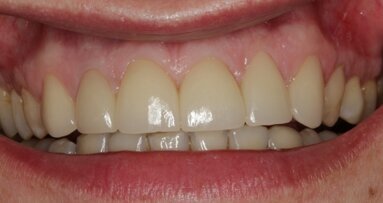

Leczeniu protetycznemu braków zębowych w odcinku przednim stawianych jest wiele wymagań nie tylko funkcjonalno-czynnościowych, ale także ...